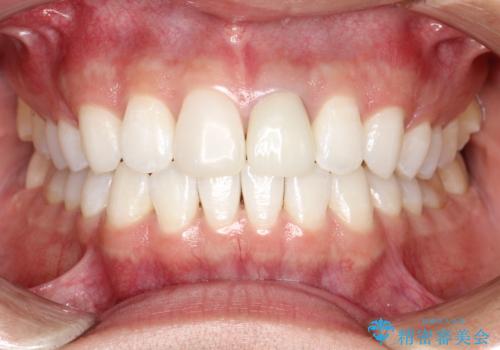

【モニター】処置歯の多い歯列 インビザラインでデコボコを整える